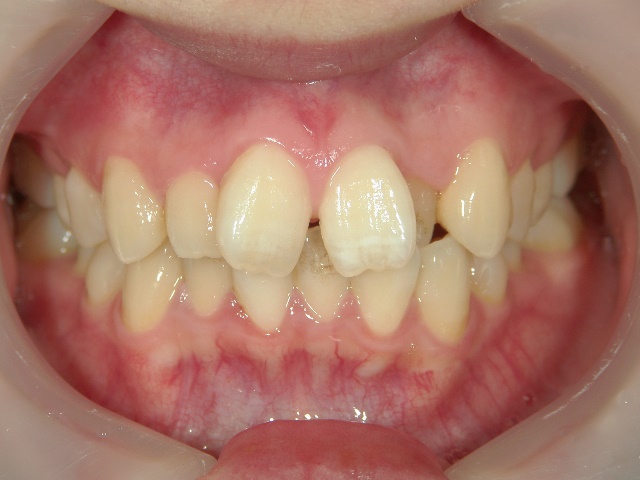

矯正歯科 治療前矯正歯科 治療前

21歳女性 浜松市北区在住

治療期間 8カ月

矯正歯科 治療前

no.8_8495_治療前_左.jpgno.8_8495_治療前_正面.jpgno.8_8495_治療前_右.jpg